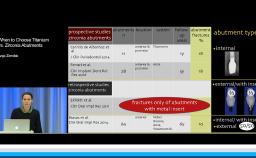

- recognize the ideal abutment design for soft tissue esthetics using CAD/CAM technology